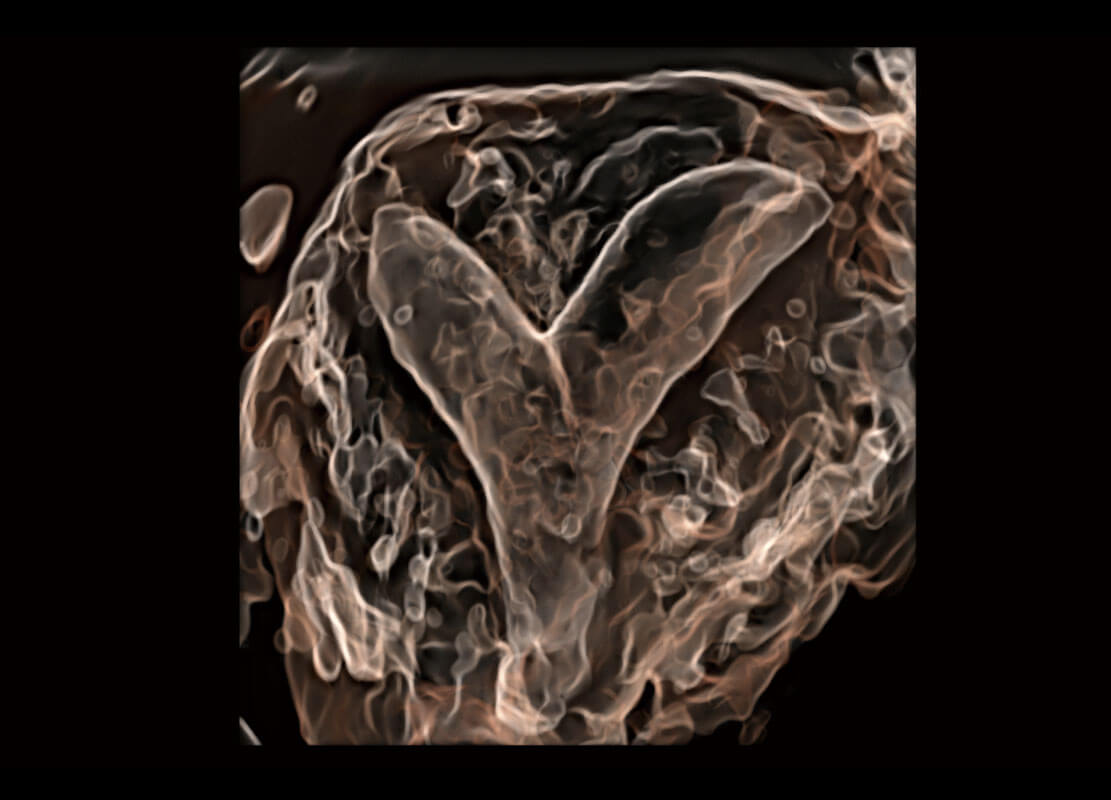

腔内三维-光影成像

胎心容积成像